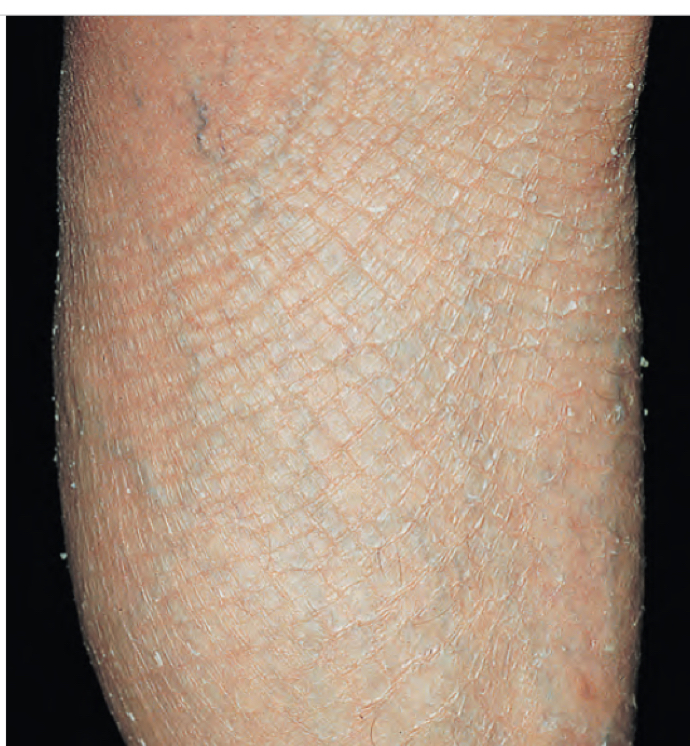

• “Fish” refers to fish like scales

• Mild-moderate scaling on the extensor extremities

Ichthyosis vulgaris

• Filaggrin deficiency = impaired formation of cornified keratinocytes

• increases your loss of epidermal water

• much more likely to have inflammatory rxn when exposed to irritants or allergens

• diagnosis:

• clinical diagnosis

• tx:

• Emollients or keratolytic agents